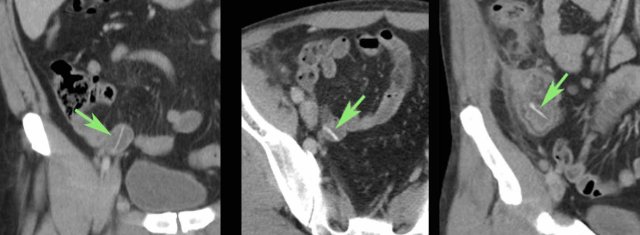

Man of 79 years old, two days hospitalized for myocardial infarction, suddenly developed pain in the RLQ and a CRP of 70, suspect for appendicitis.

He was nursed in isolation for suspected MRSA.

US showed a normal appendix of 4 mms and wall thickening of the terminal ileum, surrounded by inflamed fat (*).

Next to the ileum a possible air bubble (green arrow) was observed.

Within the ileal lumen, a linear reflective structure (arrowheads) was found.

The aspect in multiple planes, suggested a flat foreign body.

On one end, a apparently sharp edge (white arrow) stuck out into the surrounding inflamed fat (*).

Axial CT confirmed the US findings and identified an odd-looking foreign body.

On coronal CT the odd-looking foreign body had the same shape.

Try to figure out, what it is ...

And then continue reading